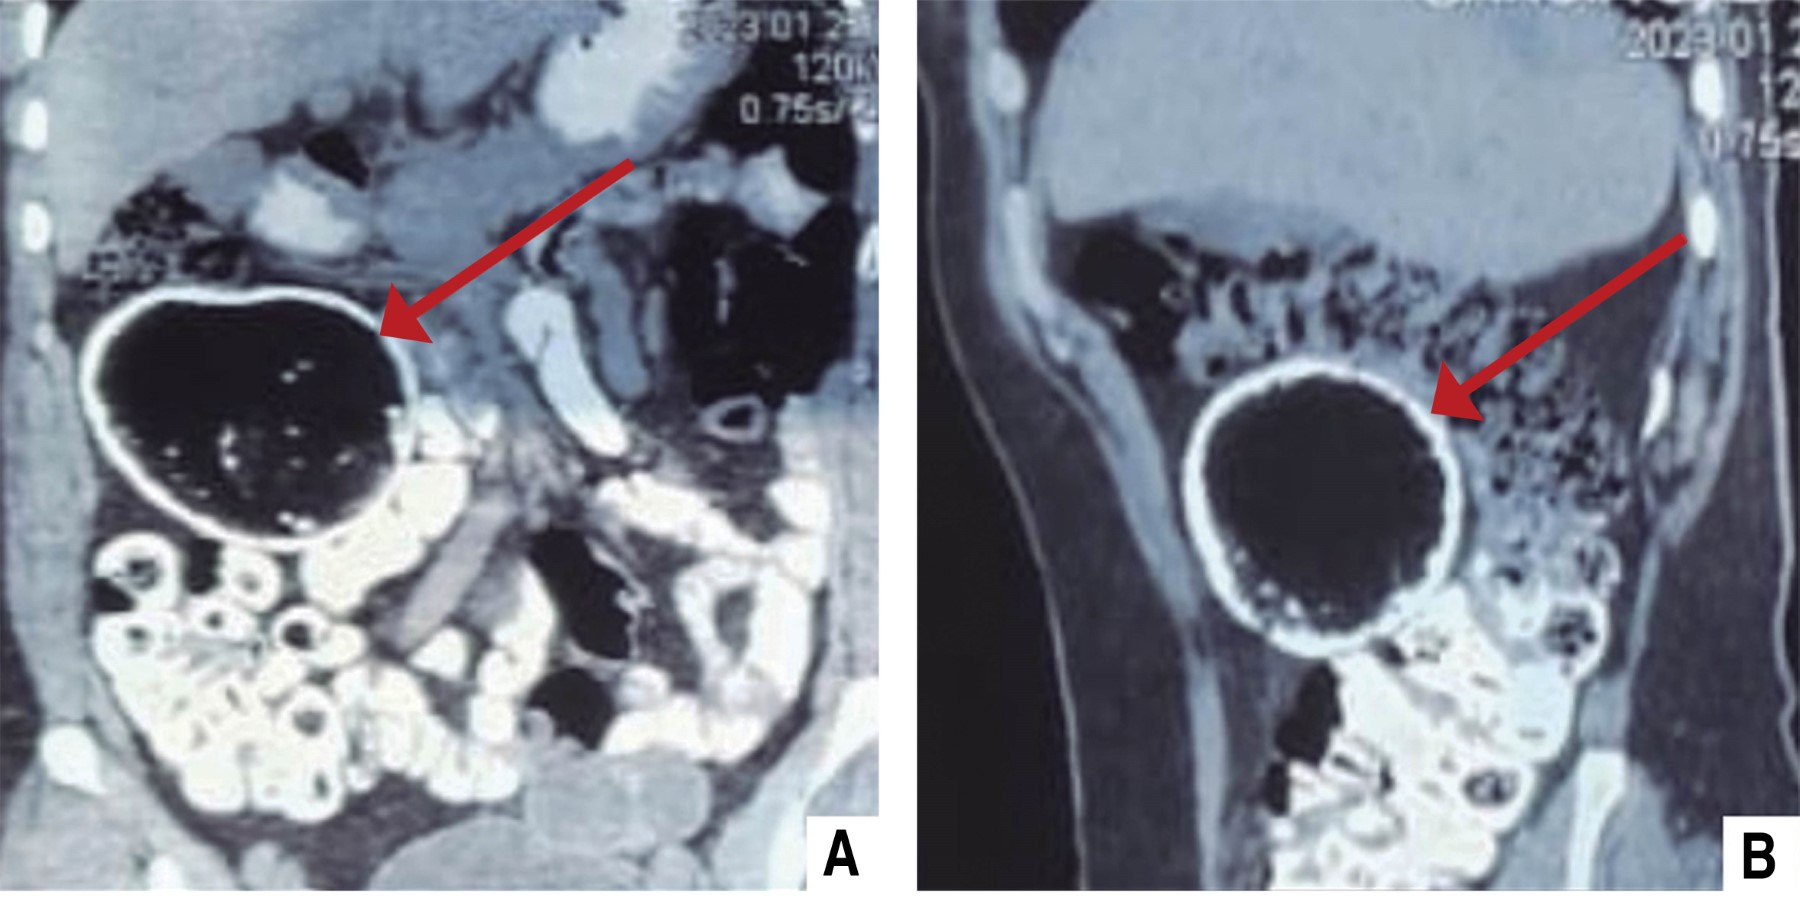

En la exploración física se identificó una masa palpable en el hipocondrio derecho y mesogastrio, de aproximadamente 15 × 15 cm, de consistencia indurada, parcialmente móvil y con sensibilidad a la palpación. No se observaron signos de irritación peritoneal ni otras alteraciones significativas. La evaluación inicial mediante ultrasonografía abdominal evidenció una lesión mixta predominantemente quística, sin vascularidad aparente, con un tamaño estimado de 85 × 74 × 67 mm y un volumen aproximado de 224 ml. Posteriormente, la tomografía computarizada con contraste confirmó la presencia de una lesión quística compleja de 8 cm3 sin datos sugestivos de infiltración a estructuras adyacentes ni características de malignidad (Figura 1), así como el hallazgo incidental de una lesión quística simple localizada en el ovario izquierdo. Los niveles séricos de marcadores tumorales, incluyendo CA-125 (10.9 U/ml), CA 19-9 (10.2 U/ml), alfafetoproteína (2.85 ng/ml) y antígeno carcinoembrionario (1.92 ng/ml), se encontraron dentro de límites normales, lo que redujo significativamente la probabilidad de malignidad.

El diagnóstico por imágenes es fundamental para identificar y caracterizar estas lesiones. En este caso, la tomografía computarizada permitió identificar una masa encapsulada con características altamente sugestivas de teratomas maduros, como calcificaciones y contenido graso.8 Estos hallazgos, descritos ampliamente por Zahid, son esenciales para diferenciar los teratomas de otras masas abdominales como quistes mesentéricos, liposarcomas y linfangiomas.9 Por otro lado, los marcadores tumorales, incluyendo CA-125 y alfafetoproteína, se encontraron en niveles normales en esta paciente, lo cual es congruente con la mayoría de los teratomas maduros descritos. Sin embargo, algunos casos reportan ligeras elevaciones de estos marcadores, lo que puede generar confusiones diagnósticas iniciales, como ocurrió en un caso documentado por Yoshida donde inicialmente se diagnosticó de manera errónea un quiste ovárico.10

Figura 1